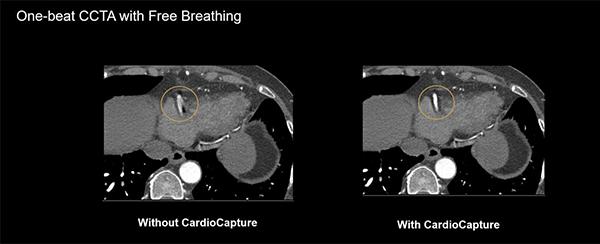

●CardioCapture

AI技術を利用し,冠動脈の動きを追跡,自動的に抽出し,動きを補正する。

Motion correctionの有無による画像の違い